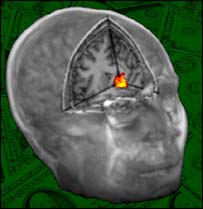

Dar bronca ativa região do prazer no cérebro, diz estudo

Em um artigo para a revista especializada Science, os pesquisadores disseram que dar uma bronca em alguém ativa uma parte do cérebro que está ligada à diversão e à satisfação.

Os cientistas concluíram que a decisão de dar uma bronca ativava uma região do cérebro conhecida por envolver os sentimentos de diversão e satisfação.